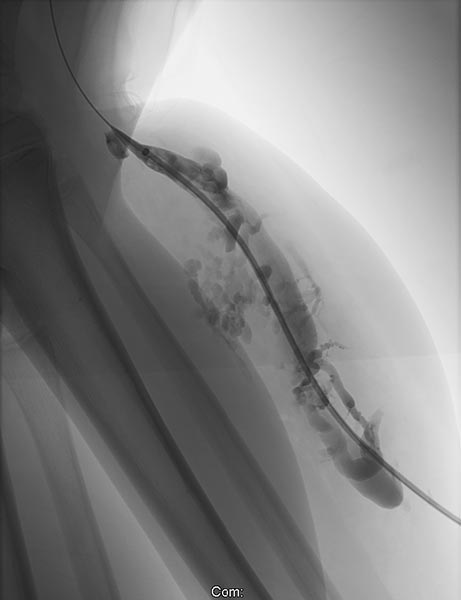

Nach Verschluss durch die Laserfaser und Anspritzen über die zurückgezogene Schleuse kommt es nicht mehr zu einem Abstrom des Kontrastmittels über die Kommunikationsvene, die erfolgreich verschlossen ist. Es kontrastiert sich nur noch die venöse Malformation. Diese ist jetzt bereit zur Sklerosierungsbehandlung, da dieses nicht mehr abfließen kann.

Auch nach zusätzlicher Punktion des ganz distalen Anteils der großlumigen Kommunikationsvene zeigt sich kein Abstrom mehr ins tiefe Leitvenensystem. Somit ist auch im Langfristverlauf die Gefahr gebannt, dass es zur Embolie von Thromben aus der venösen Malformation in zentrale Venen kommt.